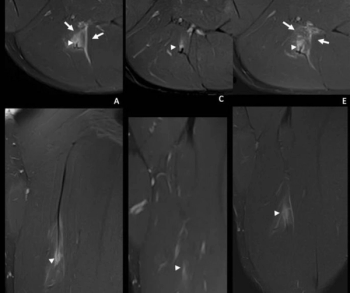

Researchers showed that adjunctive use of a deep learning algorithm resulted in an eight percent increase in sensitivity and a nearly 10 percent increase in specificity for differentiating between colon carcinoma and acute diverticulitis on computed tomography (CT) scans.